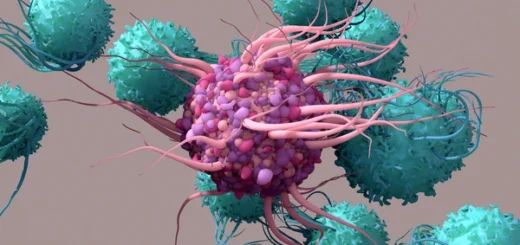

Los estímulos mayores son la cirugía, el traumatismo, las quemaduras y la infección. La respuesta local incluye a los mediadores de la inflamación como mecanismo inespecífico de defensa que desencadena el síndrome de respuesta inflamatoria sistémica.

Las proteínas de la matriz extracelular participan en la respuesta inflamatoria mediada por receptores tipo Toll (TLR) que aparece después de la lesión hística.

Los proteoglucanos, glucosaminoglucanos y glucoproteínas, como la fibronectina, han sido implicadas como participantes fundamentales en la respuesta a la inflamación.

Los proteoglucanos activan los inflamasomas intracelulares que desencadenan la inflamación estéril. El biglucano es uno de los primeros proteoglucanos descritos como ligando de los receptores tipo Toll que activan la respuesta inflamatoria a la lesión.

El biglucano se encuentra normalmente unido a la matriz extracelular, sin embargo ante una lesión de los tejidos, este se libera de la matriz en una forma soluble, para interactuar posteriormente con los receptores TLR2 o TLR4 generando una respuesta inflamatoria inmediata.